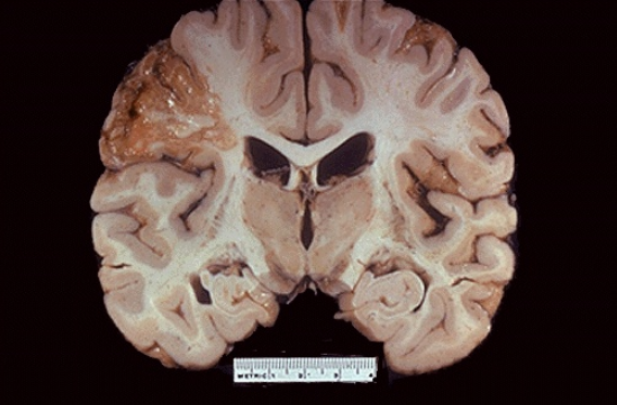

Distintas formas de muerte celular generan patrones específicos en el Sistema Nervioso Central (SNC). La destrucción de tejido produce necrosis, caracterizada por una digestión enzimática completa. ¿Cómo se denomina el tipo de necrosis que se observa?

Necrosis Licuefactiva cerebral

-Se caracteriza por la disolución parcial o completa del tejido muerto y su transformación en una masa líquida

-En el corte histológico se observa material eosinófilo amorfo.

Gran infiltrado de células inflamatorias

Especialmente neutrófilos, que liberan enzimas y contribuyen a la digestión.

Formación de cavidades llenas de líquido o pus

En infecciones puede formarse un absceso.